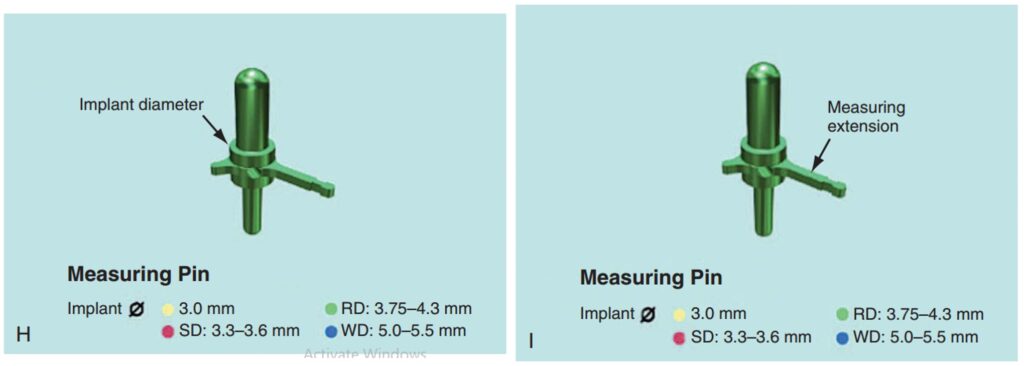

Giúp xác định đúng vị trí đặt Implant và lựa chọn đường kính Implant tối ưu nhất (H2.18). Bộ hướng dẫn ITT gồm có:

– Pin đo đạc có phần mở rộng, giúp hướng dẫn đường kính và vị trí Implant ở bệnh nhân không răng.